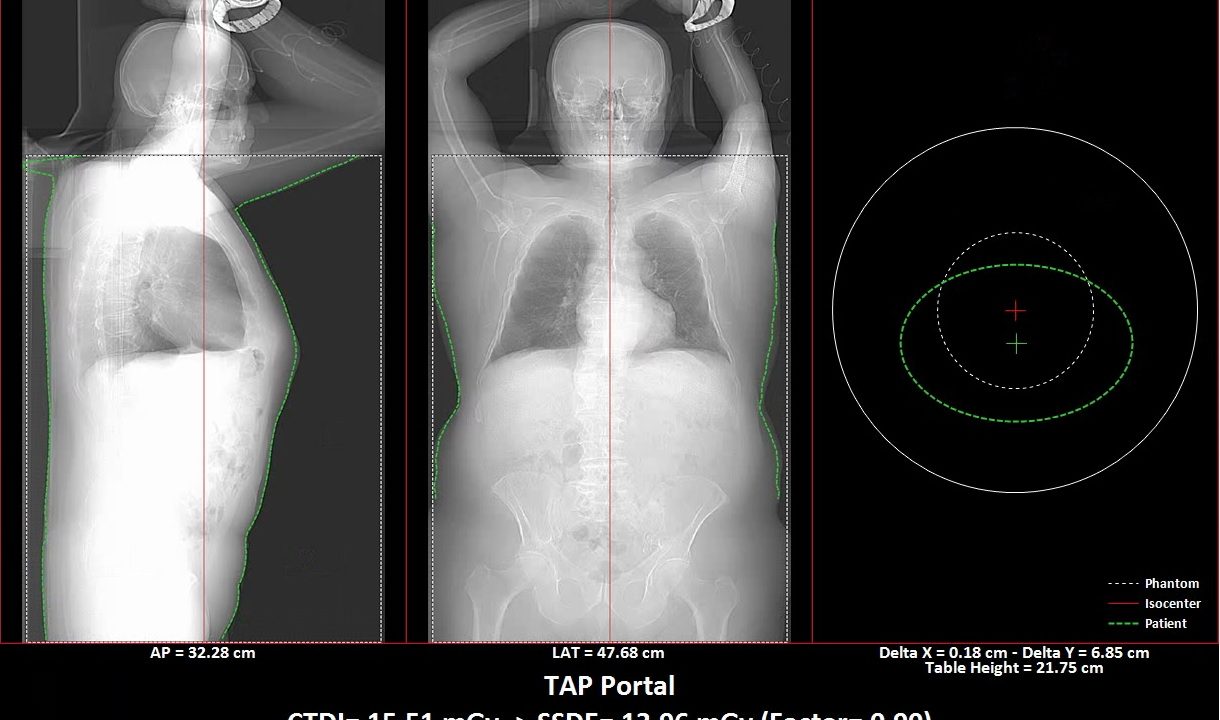

Patient ISO center